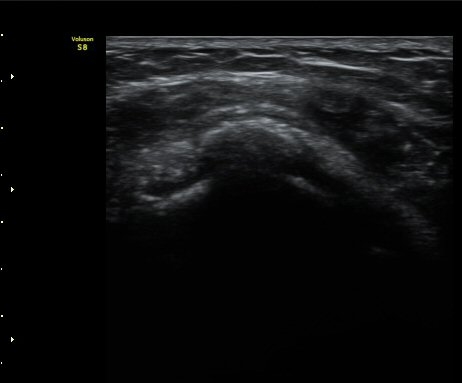

ÀδëÀÇ ºñÈİ¡ °üÂûµÈ´Ù(»çÁø 4). ±Ø»ê°ÇÀÇ Á¾´Ü¸é°Ë»ç¿Í Ⱦ´Ü¸é°Ë»ç¿¡¼­ ±Ø»ê°Ç ½ÉÃþ¿¡

Àú¿¡ÄÚ º´º¯ÀÌ °üÂûµÈ´Ù(»çÁø 5, 6).